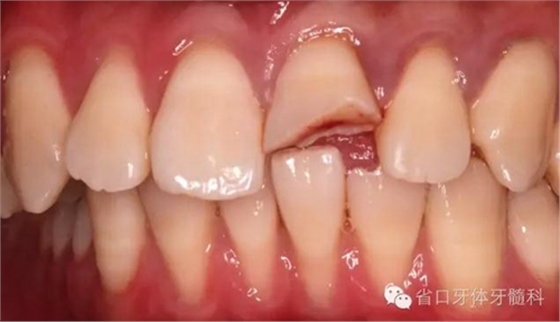

口內(nèi)檢查:21切1/3-1/2折斷,髓腔暴露,探痛明顯

近中鄰面探及齲損,松-,叩+,齦緣輕度紅腫,探及齦下結(jié)石。

術(shù)前口內(nèi)照

斷冠